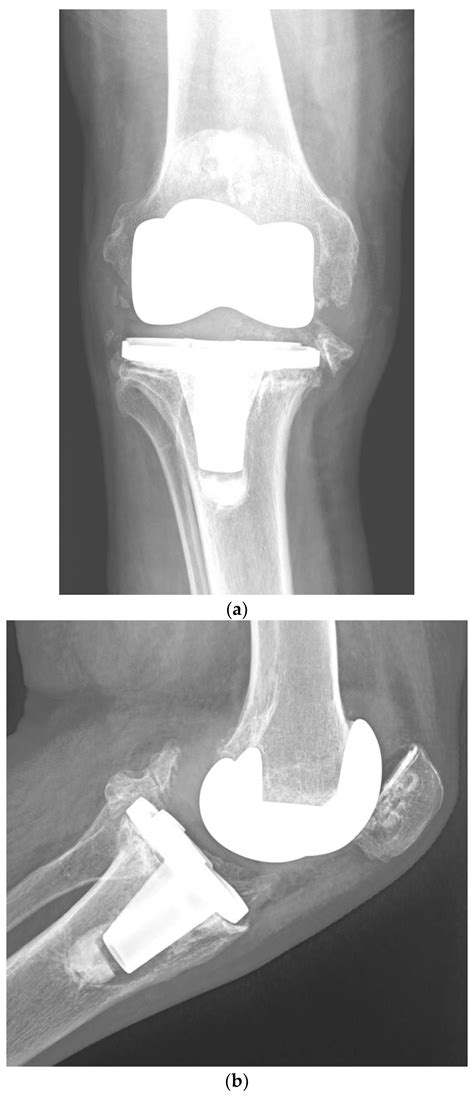

Total knee arthroplasty, or knee replacement, is a highly successful surgery designed to relieve pain and restore function in diseased or damaged knee joints. By looking at Knee Replacement Images, patients can see how an orthopedic surgeon removes the damaged cartilage and bone from the surface of the knee joint and replaces them with artificial components. These components are meticulously crafted to mimic the natural movement of a healthy knee.

The surgery generally involves three primary parts:

• The Femoral Component: A metal piece that attaches to the end of the thigh bone (femur).

• The Tibial Component: A metal tray that sits on top of the shin bone (tibia).

• The Patellar Button: A plastic piece that replaces the surface of the kneecap.